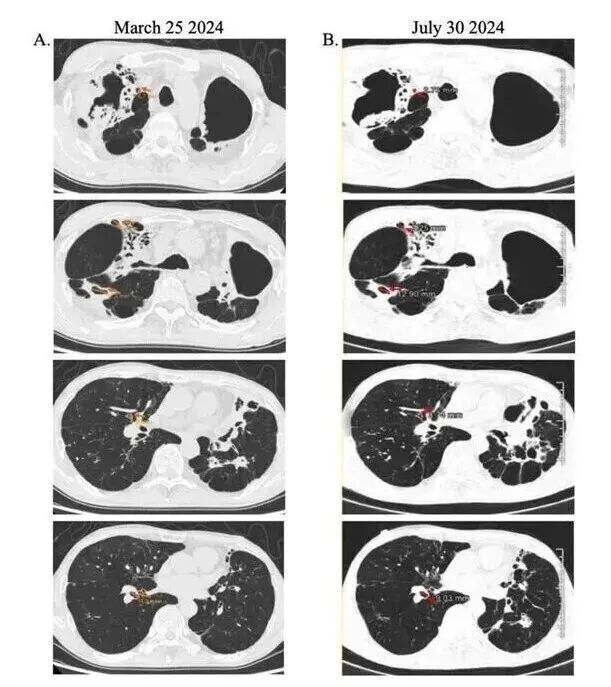

放射学证据则佐证,实施呼气式吸入疗法后,呼吸道腔隙缩小情况突出,对比病灶基线期扫描结果,后续检测可见腔隙尺寸显著减小(红色箭头指示)。